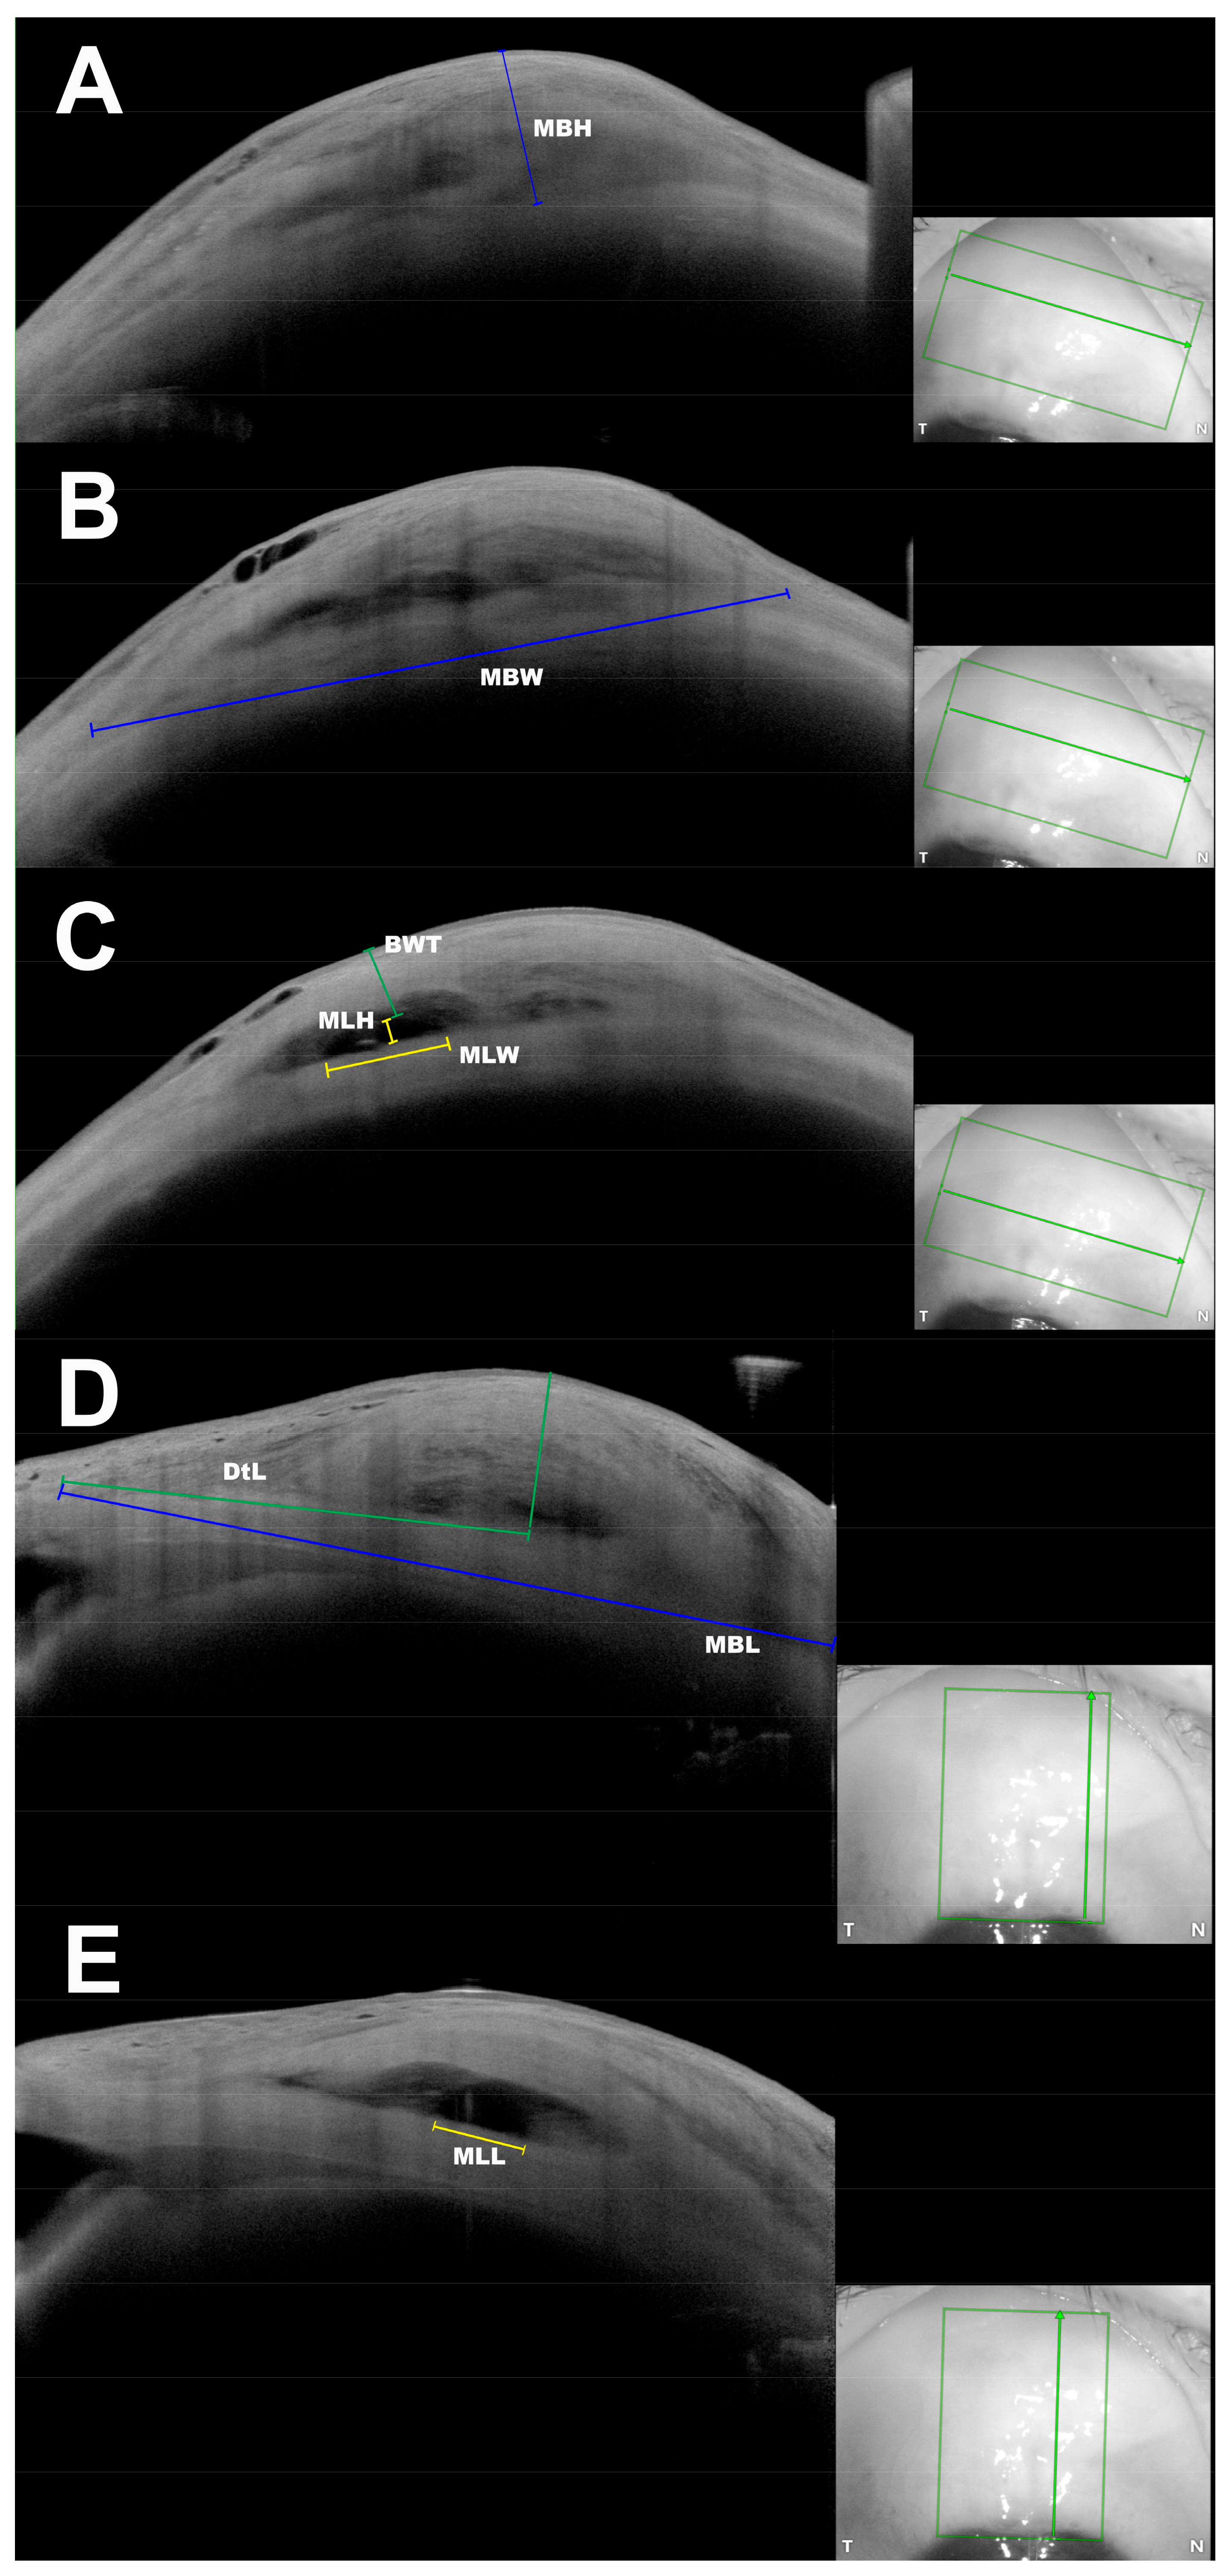

Maximum Bleb Height Figure 1A | MBH | The maximum height of the bleb seen in the tangential scans, measured as the maximum perpendicular distance from the sclera to the first reflex at the conjunctiva. | |

Maximum Bleb Width Figure 1B | MBW | The maximum width of the bleb seen in tangential scans, measured as a direct line between two points: begin of changes in tenon thickness nasally to end of tenon changes temporally. | If the whole width of the bleb could not be captured in a single image, the maximum visible width was measured. |

Maximal Bleb Length Figure 1D | MBL | The maximum posterior extension of the bleb seen in radial scans, measured as a direct line between two points: from the first changes in tenon thickness anteriorly to the last visible tenon change posteriorly. If the bleb extended over the cornea, measurement was started at the level of the scleral spur. | If the whole length of the bleb could not be captured in a single image, the maximum visible length was measured. |

Maximum Lake Height Figure 1C | MLH | The maximum height of the episcleral lake (ES1 according to JBGS) in the tangential scans, measured as maximum perpendicular distance from the inferior to the superior edge of the episcleral lake. | MLH was measurable only in blebs showing the pattern ES1. |

Maximum Lake Width Figure 1C | MLW | The maximum width of episcleral lake seen in tangential scans, measured as a direct line between two points: begin of episcleral lake nasally to its end temporally. | MLW was measurable only in blebs showing the ES1-Pattern. |

Maximal Lake Length Figure 1E | MLL | The maximum posterior extension of the episcleral lake seen in a radial scan, measured as a linear distance between two points: begin of the episcleral lake anteriorly to its end posteriorly. | If the whole length of the episcleral lake could not be captured in a single image, the maximum visible length was measured. |

Bleb Wall Thickness Figure 1C | BWT | Minimal thickness of the bleb wall at the scan with the MLH, measured as the minimal perpendicular distance between the end of the episcleral lake and the first reflex at the conjunctiva. | BWT was measurable only in blebs showing the ES1-Pattern. |

Distance to Limbus Figure 1D | DtL | The linear distance between two points: point of corneal surface corresponding to the scleral spur and point of scleral surface corresponding to the highest point of the bleb in radial scans. |